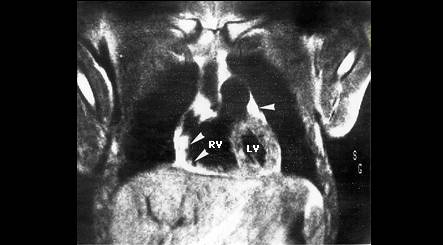

Ecocardiografia si angiografia cu radionuclizi (ARN) evidentiaza dilatatia si hipokinezia sau diskinezia difuza a VD.

Rezonanta magnetica nucleara este caracteristica, evidentiind dilatatia si hipokinezia VD.